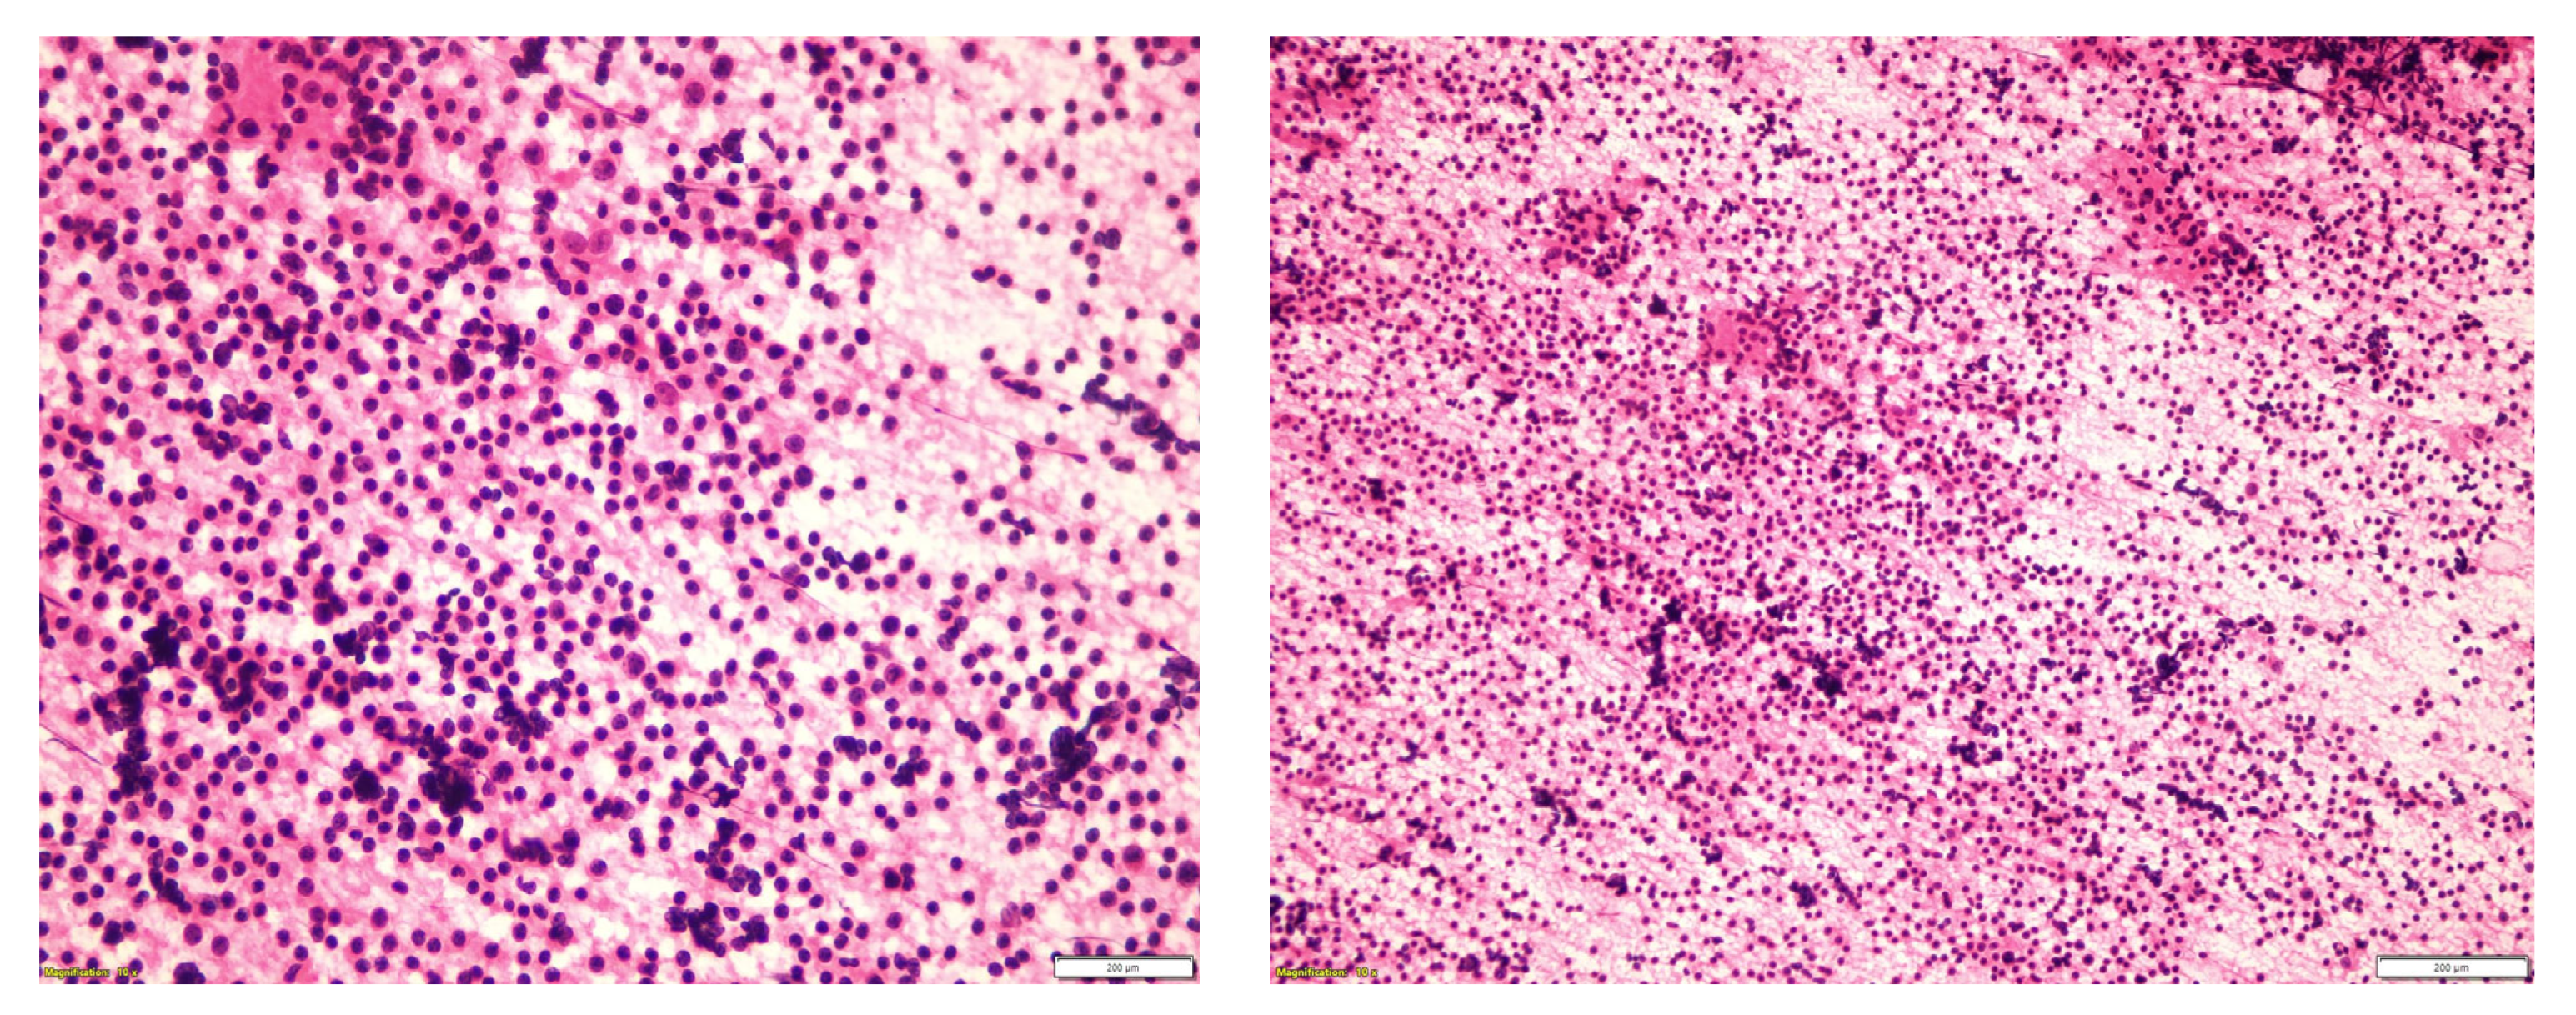

| Current case | 64 | M | Right parotid | WT | Follicular lymphoma/grade 1–2 |